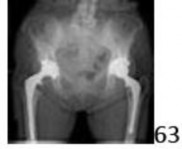

63 An 83-year-old patient has had a 6-month history of right groin pain. History reveals that hip arthroplasty was performed 14 years ago. An AP radiograph is shown in Figure 63. Preoperative evaluation reveals no evidence of infection. Which of the following studies is the next most appropriate step in evaluation?

DISCUSSION: The patient has a single radiograph for interpretation. To thoroughly evaluate the symptom of groin pain, additional radiographic

views are appropriate. Judet views will show the integrity of the posterior column. Cross table lateral radiographs do not provide adequate visualization of the acetabulum for osteolysis. CT would most definitively show the extent of osteolyis, but it is not one of the options. MRI would have too much metal artifact. A bone scan could suggest loosening, but initial radiographic studies are more appropriate to obtain first in assessment. Dynamic fluoroscopy is not normally used in the assessment of implant failure. The Preferred Response to Question # 63 is 4.